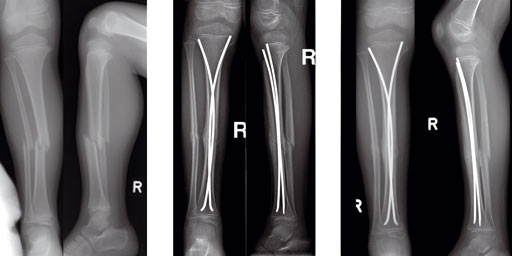

Fig 13a-b: X-rays show a long spiral fracture of the proximal third of the right femur (32D/5.1). Because of the age good indication for ESIN, but some danger of instability is possible.

Fig 13c-d: Postoperative x-rays. A closed reduction and fixation with 3.0 mm TEN was carried out with correct child-oriented alignment. For stability reasons two End Caps became uses. No signs of a shortening can be seen.

Fig 13e-f: AP and lateral view 6 weeks after surgery shows good callus formation and still a perfect alignment.

Full weight bearing was then allowed.